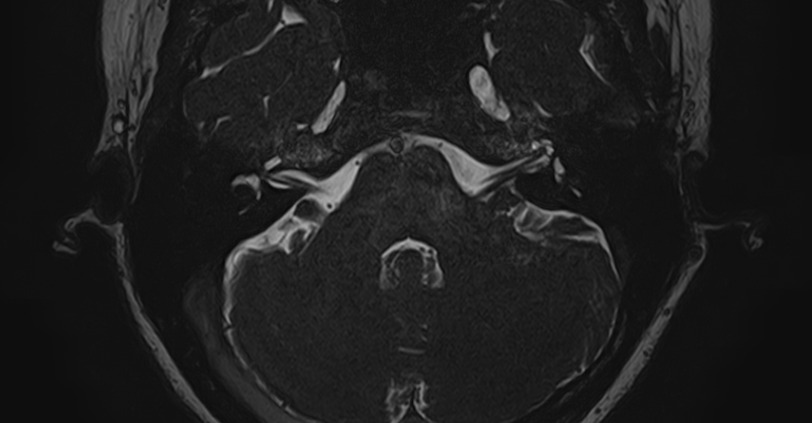

Внутреннее ухо – важная часть слуховой и вестибулярной систем тела человека, находящаяся в толще пирамиды височной кости.

Внутреннее ухо содержит слуховой орган (улитку) и орган равновесия (преддверие и полукружные каналы), патологические изменения которых в свою очередь приводят к развитию нейросенсорной тугоухости и вестибулярных нарушений.